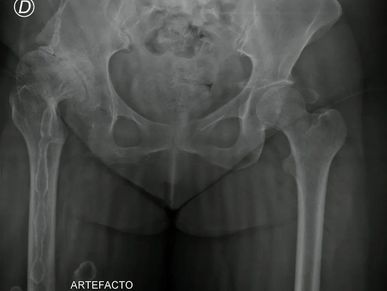

Mirá cómo recuperamos la movilidad en un caso de artrosis severa y deformidad acetabular mediante tecnología 3D de alta precisión. Planificación preoperatoria en 3D para cirugía de cadera con artrosis severa e importante deformidad acetabular. Se imprimieron biomodelos en 3D y guías para la correcta colocación de los componentes protésicos. De esta manera, se logró restaurar la longitud de las piernas y se eliminó el dolor invalidante que presentaba el paciente.

Paciente con artrosis severa y deformidad ósea que dificultaba la colocación acetabular. Con tomografía realizamos planificación 3D y diseñamos una guía quirúrgica personalizada impresa en 3D. En quirófano replicamos el plan: posicionamiento preciso del componente y restauración del centro de rotación. La tecnología 3D aporta más precisión, seguridad y predictibilidad en casos complejos.